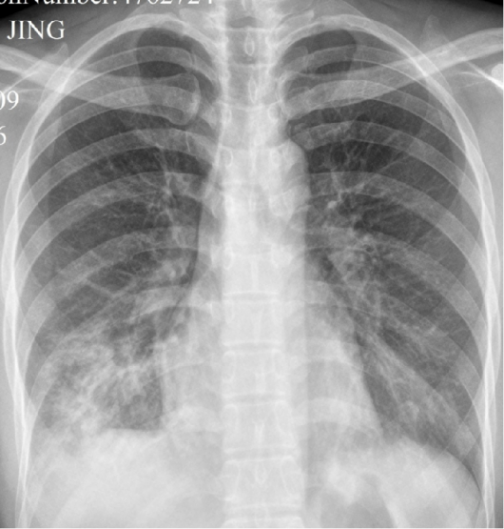

图 7. 患有肺炎支原体肺炎的 14 岁男孩的胸部 CT:a.轴向对比增强 CT 扫描(5 mm 层厚)显示右下叶有肺段实变,伴有少量胸腔积液。空气支气管征很好地表明了实变;b.高分辨率 CT(1 mm 层厚)的肺窗图像显示在肺段实变周围具有小叶中心结节和腺泡结节的片状肺叶实变(箭头).

图 8. 20 岁男性肺炎支原体肺炎的胸部 CT:a.高分辨率 CT(1.25 mm 层厚)的肺窗图像显示两肺弥散斑片状的磨玻璃样密度影。注意支气管壁的轻度弥漫性增厚(箭头);b.在较低等级下获得的肺窗图像显示两肺中斑片状的磨玻璃样密度影。在左下叶显示了小叶中心结节的周围磨玻璃样密度影。注意小的融合性支气管周围实变(箭头)和小叶间隔增厚(箭头)